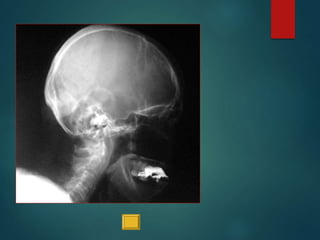

Este documento proporciona instrucciones para realizar diferentes proyecciones radiográficas del cráneo, incluyendo las proyecciones anteroposterior (AP), submentovertex (SMV), parietoorbitaria y transorbitaria de Guillen. Describe los ángulos y posiciones requeridos para cada proyección y las estructuras óseas que deberían ser visibles en cada imagen resultante.